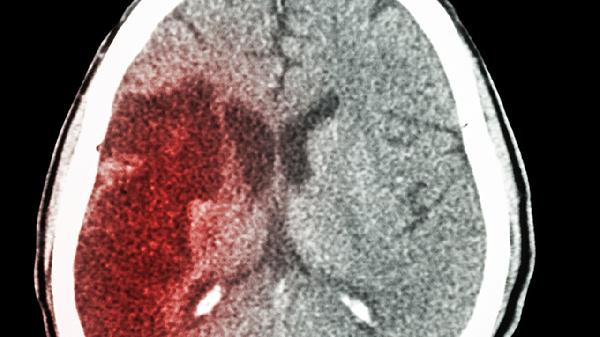

腿麻可能是脑出血吗

腿麻并不一定意味着是脑出血,也可能是由腰椎间盘突出、糖尿病周围神经病变、下肢血管问题、短暂性脑缺血发作或电解质失衡等引起的。如果是因为脑出血导致的腿麻,通常会伴随着剧烈头痛、恶心呕吐以及意识模糊等症状。